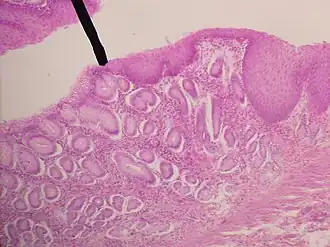

Le pareti dell'esofago sono formate da strati, o tonache, sovrapposte: mucosa, sottomucosa, tonaca muscolare e tonaca avventizia. La mucosa esofagea è uno strato spesso, di colore grigio-rosato o rossastro nella giunzione gastro-esofagea; a riposo presenta numerosi solchi e creste, tali da occluderne il lume. Si tratta però di modificazioni temporanee della mucosa esofagea che scompaiono quando questa è distesa, per esempio durante il passaggio del bolo alimentare. In sezione trasversale, il lume esofageo appare stellato in stato di deplezione.

L'epitelio della mucosa esofagea è pavimentoso pluristratificato, non cheratinizzato e continuo con quello della faringe. Ha uno spessore di 400-500 µm, ed è interdigitato con la lamina propria sottostante. Ciò lo rende facilmente distinguibile da questa e permette una migliore adesione dei due strati tissutali, che non si modificano in stato di contrazione o distensione. Gli strati più superficiali presentano cellule squamose ed appiattite, provviste di nucleo cellulare tondeggiante, nel cui citoplasma sono presenti filamenti di cheratina e scarsi granuli di cheratoialina.

La mucosa è costituita da tre strati: epitelio di rivestimento (di tipo pavimentoso stratificato non cheratinizzato), tonaca propria e muscularis mucosae.

Lo strato più esterno della parete esofagea è muscolare (muscularis propriae), ed è costituito da fibre muscolari di tipo striato (volontarie) nel terzo superiore, da fibre muscolari lisce (involontarie) nel terzo inferiore mentre nel terzo medio la muscolatura è mista in quanto sia ha il passaggio da un tipo all'altro. Per tutta la lunghezza comunque le fibrocellule muscolari sono organizzate in due strati: uno con fibre ad andamento circolare (più interno) ed uno con fibre ad andamento longitudinale (più esterno); durante la deglutizione questi muscoli si contraggono, spingendo il cibo nello stomaco (peristalsi). Nello strato intermedio, invece, si trovano le ghiandole esofagee (ghiandole cardiali), che versano la loro secrezione nel lume dell'esofago. Questo secreto permette di mantenere umido l'esofago. Tra le fibrocellule muscolari lisce sono presenti fibre nervose appartenenti al plesso mioenterico dell'Auerbach che stimola la peristalsi esofagea. La sottomucosa presenta connettivo lasso con ghiandole tubuloacinose ramificate mucose e fibre nervose del plesso del Meissner che regolano la secrezione ghiandolare e la motilità della muscolaris mucosae. La lamina propria è riccamente vascolarizzata e si solleva in pieghe.